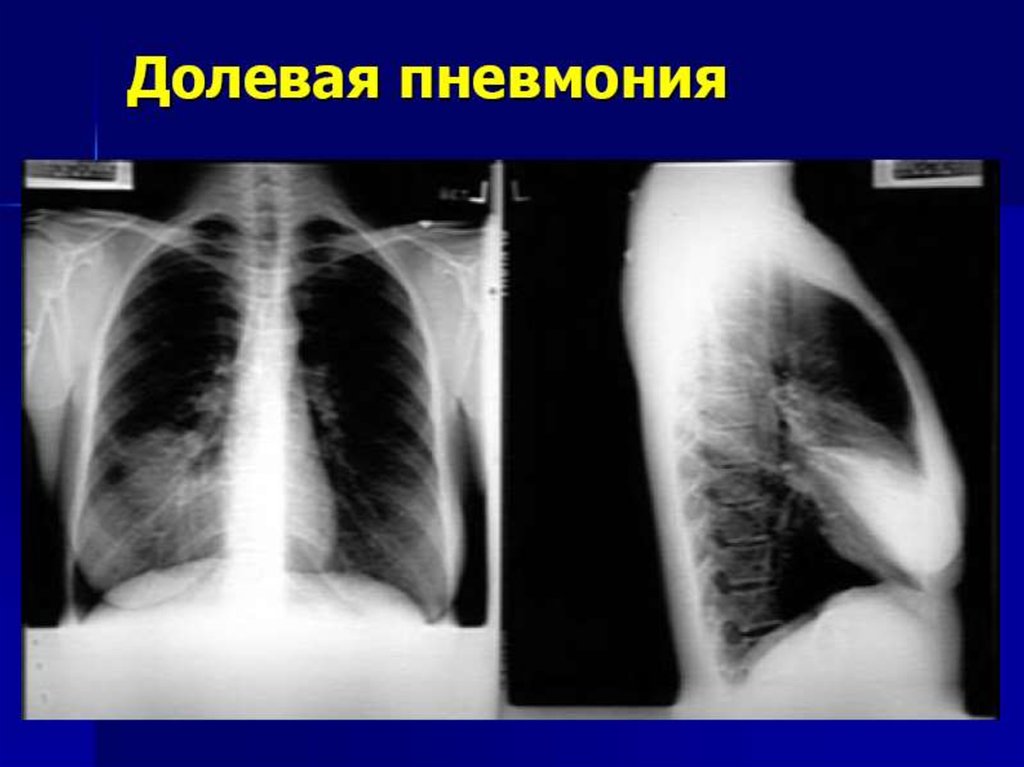

26. Рентгенологическая картина

Долевая (крупозная) пневмония